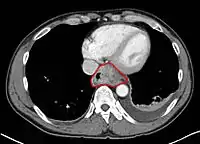

Anatomy

• Mucosa: epithelium, lamina propria, muscularis mucosa. Separated by basement membrane from rest of esophageal wall

• Submucosa: fibroelastic fibers, nervous plexuses, glands

• Muscularis propria: inner circular muscle layer, outer longitudinal muscle layer

• Adventitia: dense periesophageal connective tissue

• The serosa only lines the intra-abdominal esophagus

• Resectability often limited:

• Lack of fibrous serosa to prevent local spread

• Rich lymphatic network in submucosa and muscularis that allows longitudinal and circumferential drainage